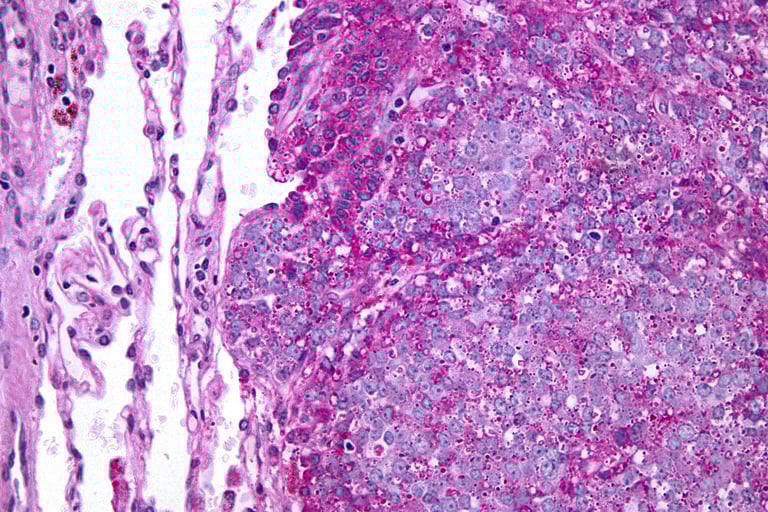

Resim 2. Ewing sarkomu tanısı patolojik inceleme ile konulur ve EWS-FLI1 füzyonu sıklıkla saptanır.

Klasik Ewing Sarkomu: En yaygın görülen türdür. Mikroskop altında küçük, yuvarlak, mavi hücreler şeklinde karakterize edilir. Bu hücreler genellikle yoğun bir şekilde düzenlenmiştir ve spesifik translokasyonlar içerirler.

Bu patolojik tiplerin her biri, mikroskop altında incelemeler ve genetik testler ile belirlenir. Tedavi planlaması ve prognoz (hastalığın gidişatı tahmini) için tümörün patolojik tipinin belirlenmesi önemlidir. Her tür benzer tedavi yaklaşımlarını gerektirse de bazı durumlarda farklı tedavi stratejileri gerekebilir. Bu nedenle, Ewing Sarkomunun patolojik tipinin doğru bir şekilde tanımlanması, hastanın tedavi sürecinde kritik bir rol oynar. Ewing Sarkomunun tanı ve tedavisinde, tümör hücrelerinde bulunan çeşitli reseptörler ve moleküler markırların incelenmesi büyük önem taşır. Bu kanser türünde, özellikle genetik ve moleküler düzeyde ön plana çıkan bazı kilit reseptörler ve proteinler şunlardır: CD99 genellikle Ewing Sarkom hücrelerinde yüksek düzeyde ifade edilen bir yüzey proteinidir ve bu tümörün tanımlanmasında ana belirteçlerden biri olarak kabul edilir. EWS-FLI1 Füzyon Proteini, çoğu Ewing Sarkomunda bulunan ve kromozomal translokasyonun sonucunda oluşan önemli bir moleküler hedeftir. IGF-1 Reseptörü (İnsulin-like Growth Factor 1), tümörün büyümesi ve yayılmasıyla ilişkili olduğu düşünülen başka bir kritik moleküler hedeftir. VEGF (Vasküler Endotelyal Büyüme Faktörü), tümör hücrelerinin yeni kan damarları oluşturarak beslenmesine ve büyümesine yardımcı olan bir faktördür ve VEGF'e yönelik tedaviler, tümörün kan akışını azaltmayı ve böylece büyümesini sınırlamayı hedefler. NKX2.2 ise, EWS-FLI1 füzyon proteininin düzenlediği genlerden biri olup, bazı Ewing Sarkomlarında yüksek düzeyde bulunur ve potansiyel bir tedavi hedefi olarak görülür.